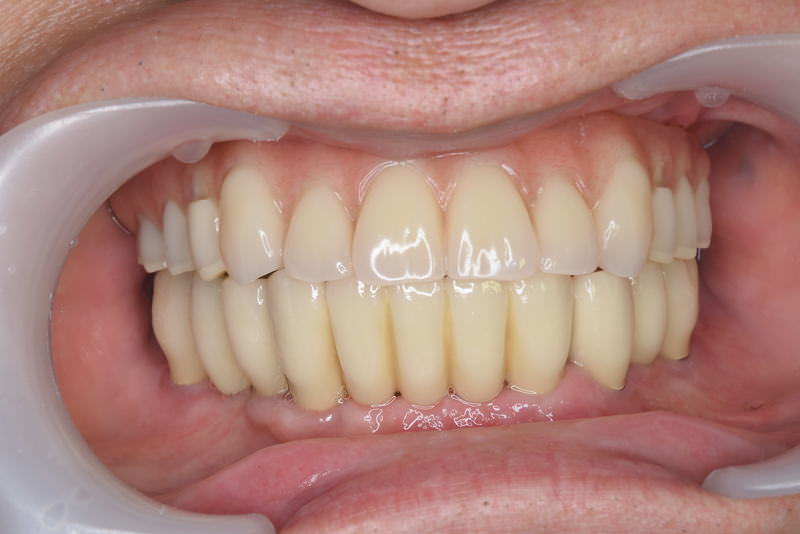

症例3【60代女性】主訴 審美障害・義歯がわずらわしい

治療後(3年経過)

治療後

※説明

主訴 上下の部分義歯が煩わしい、しっかり奥歯で噛めないと訴え来院。

上顎前歯部、左上臼歯部にはブリッジが装着されていて、支台歯に負担がかかっており、力学的配慮設計を重視し、固定制のインプラントを提案。

前歯部、小臼歯部には、造骨、歯肉移植も含めた幅の確保をし、永続性のある土壌作りを行った。

免荷期間中は、QOLを損なわない為に、ミニインプラント(即時荷重)を埋入、オペ当日に仮歯を装着し、咀嚼可能にした。

最終補綴物装着までの期間は、約8ヶ月を要した。ジルコニア(レイヤリング法)を装着。

リスクとしては、外科的侵襲がある。デメリットは、保険外診療の為、経済的負担がある。

費用 501万 (オペ・ミニインプラント・人工骨・歯肉移植・仮歯・採血による濃縮血小板生成・最終補綴物まで含む)